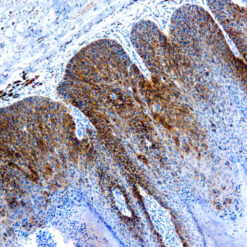

| Positive Control Tissue | Testis |